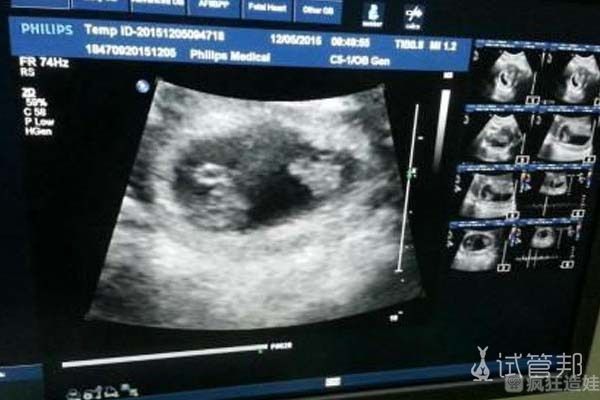

第二次取卵,医生让我用高效孕激素促排卵。这次成功取出了三个卵子,冷冻了一个胚胎。休息了一段时间后,今年1月,我胚胎移植了这个珍贵的胚胎。本来也没有报很大的希望,但令我激动的的是,胚胎移植后14天,我真的怀孕了。胚胎移植后28天,我去照了彩超,打出来竟然是双胞胎!